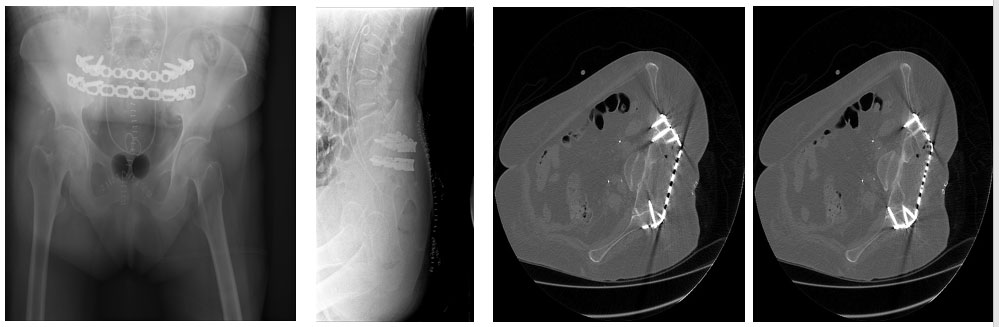

Ameliyat sonrası: Röntgen ve tomografide uygulanan titanyum plak görülmekte